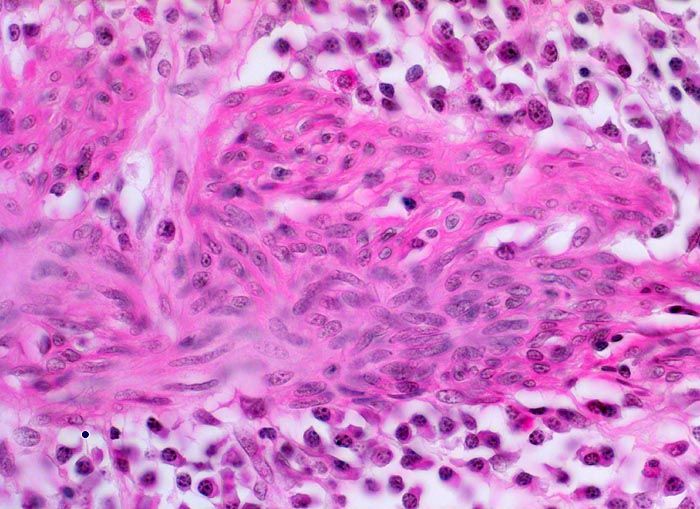

Mikroskopisch findet sich je nach Entzündungsaktivität eine mehr oder weniger ausgeprägte diffuse Verdichtung des lymphoplasmazellulären Entzündungsinfiltrates mit Beimischung von Granulozyten in Form einer Kryptitis oder von Kryptenabszessen. Bei einer stark aktiven Entzündung finden sich zusätzlich Erosionen und Ulzera mit Ausdehnung der Entzündung über die Mukosa hinaus in die Submukosa oder in noch tiefere Schichten bei hochflorider Kolitis. Die Kryptenarchitektur ist gestört, die Anzahl der Krypten und der Becherzellen vermindert. In der Regeneratphase finden sich zahlenmässig reduzierte und verkürzte Krpyten mit normaler Anzahl Becherzellen. Meist bleibt eine leichte Verdichtung der Entzündungszellen in der Lamina propria bestehen.

Basal betonte Plasmozytose und Infiltrate neutrophiler Granulozyten.

Ansammlungen neutrophiler Granulozyten in Kryptenlumina (=Kryptenabszesse) und Infiltrate von neutrophilen Granulozyten im Kryptenepithel (=Kryptitis).